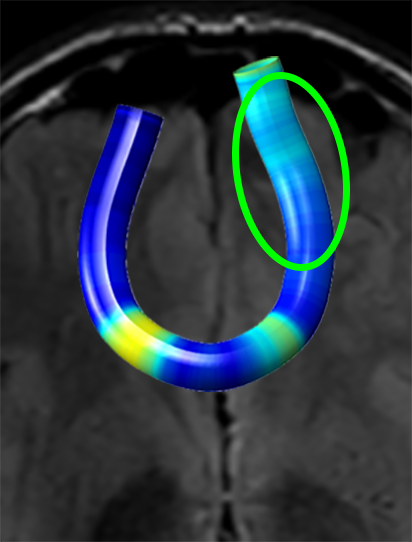

We performed pairwise comparison between two scans of a 32-year-old basketball player, diagnosed with mild occipital traumatic brain injury and frontal hemorrhage due to contrecoup impact, acquired one week and 6 months post-injury. The hemorrhagic lesion at the frontal right hemisphere of the player is no longer visible in the FLAIR image acquired 6 months after injury (Fig. 2a). Local differences between corresponding, longitudinal FA- and MD-FFDD profiles of the FMT (chosen due to its proximity to the lesion area) are shown in Fig. 2d. Figs. 2b-c present color-coded FMT to visually demonstrate these differences. Results show significant longitudinal variability at the right hemisphere part of the tract, corresponding to the lesion area, and relatively minor differences along the rest of the tract. These results should be considered as a proof of concept, validating the FFDD analysis results for the detection and localization of mTBI-related variabilities between fiber bundles.

| ONE WEEK | ![]() |

![]() |

FA-FFDD |

| 6 MONTHS | ![]() |

MD-FFDD |

| (a) FLAIR | (b) FA-FFDD | (c) MD-FFDD | (d) Local Differences |